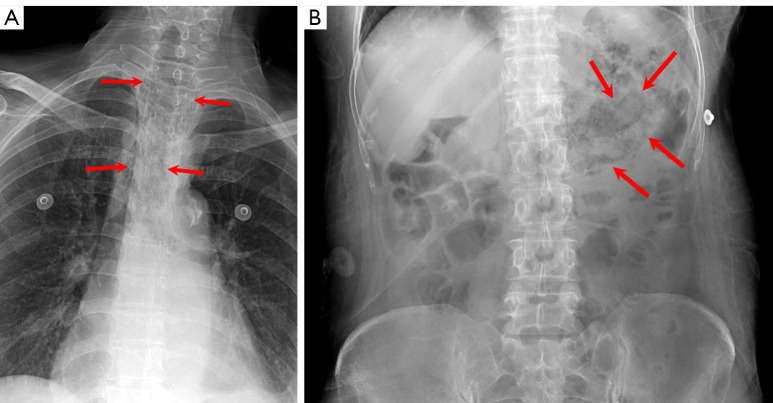

Case description: A 65-year-old woman was admitted to Inje University Sanggye Paik Hospital with general weakness, abdominal discomfort, nausea and chest discomfort. On chest and abdominal radiographs, there were abnormal air density in upper mediastinum and abdomen. Chest and abdomen computed tomography (CT) revealed mural air at entire esophagus and stomach. The patient managed with proton pump inhibitor (PPI), broad spectrum antibiotic therapy, and total parenteral nutrition (TPN).